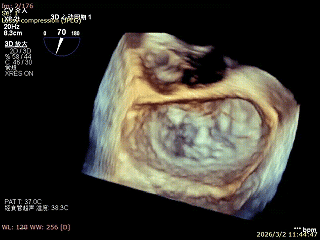

患者为房间隔缺损术后合并功能性二尖瓣反流(FMR),病变位于二尖瓣2区偏3区,因既往ASD修补史(可降解房间隔缺损封堵器),致房间隔穿刺区域存在瘢痕粘连、穿刺难度增加,于靠下靠后位置穿刺,避开房间隔缺损封堵伞,其余病变解剖结构相对简单;术前制定手术策略,拟使用1把XTR行二尖瓣修复,术中克服瘢痕粘连难点成功完成房间隔穿刺,穿刺点距二尖瓣瓣环平面3.1cm,将XTR‑CDS送入左心房,通过”A”旋钮旋转180度借高度,LVOT切面夹子严重Huge,使用”+”旋钮一键消除Huge,通过操控“M”旋钮将二尖瓣夹精准定位于2区正上方,完成弹道测试及Orientation调整后,于2区将夹子送入左心室,顺利捕捞并夹持瓣叶后缓慢闭合夹臂;TEE检查示二尖瓣反流充分降低至微量,二尖瓣双孔组织桥稳定,跨瓣压差2mmHg,肺静脉逆流明显改善,手术安全顺利结束。

双孔组织桥稳定

3D enface反流充分降低

术后平均跨瓣压差2mmHg